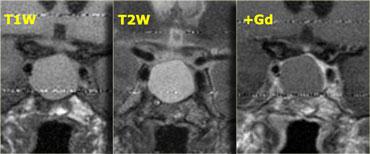

Các chuỗi xung T1W, T2W và T1W sau tiêm gadolinium này minh họa một nang khe Rathke khác nằm trong tuyến yên.

Khác với mô tuyến yên bình thường và cuống tuyến yên, nang không ngấm thuốc sau khi tiêm thuốc tương phản từ tĩnh mạch.

Mô tuyến yên bình thường bị chèn ép và đẩy lệch sang bên trái. Điều quan trọng là cần nhận biết điều này vì có thể nhầm lẫn với thành phần ngấm thuốc của khối dạng nang.

Nhìn chung, tất cả các khối ngoài trục, tức là các khối nằm ngoài não như tuyến yên và cuống tuyến yên, đều sẽ ngấm thuốc vì chúng không có hàng rào máu-não.